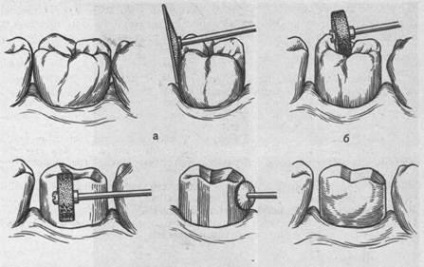

1. boncolása egy lepecsételt korona

Mint azt bizonyára tudják, a sapka vastagságát lepecsételt korona 0,3 mm. Tehát az az összeg, előkészítése. Tooth alakú henger, eltávolítjuk a 0,3 mm-es a nyak területén (ahol a párkány jön létre). Az egyenlítő boncolt, hogy hozzon létre egy farönköt egy henger alakú. Okklúziós felülete tagolt 0,3 mm, és a megközelítőleg megtartja enyhülést halmok.